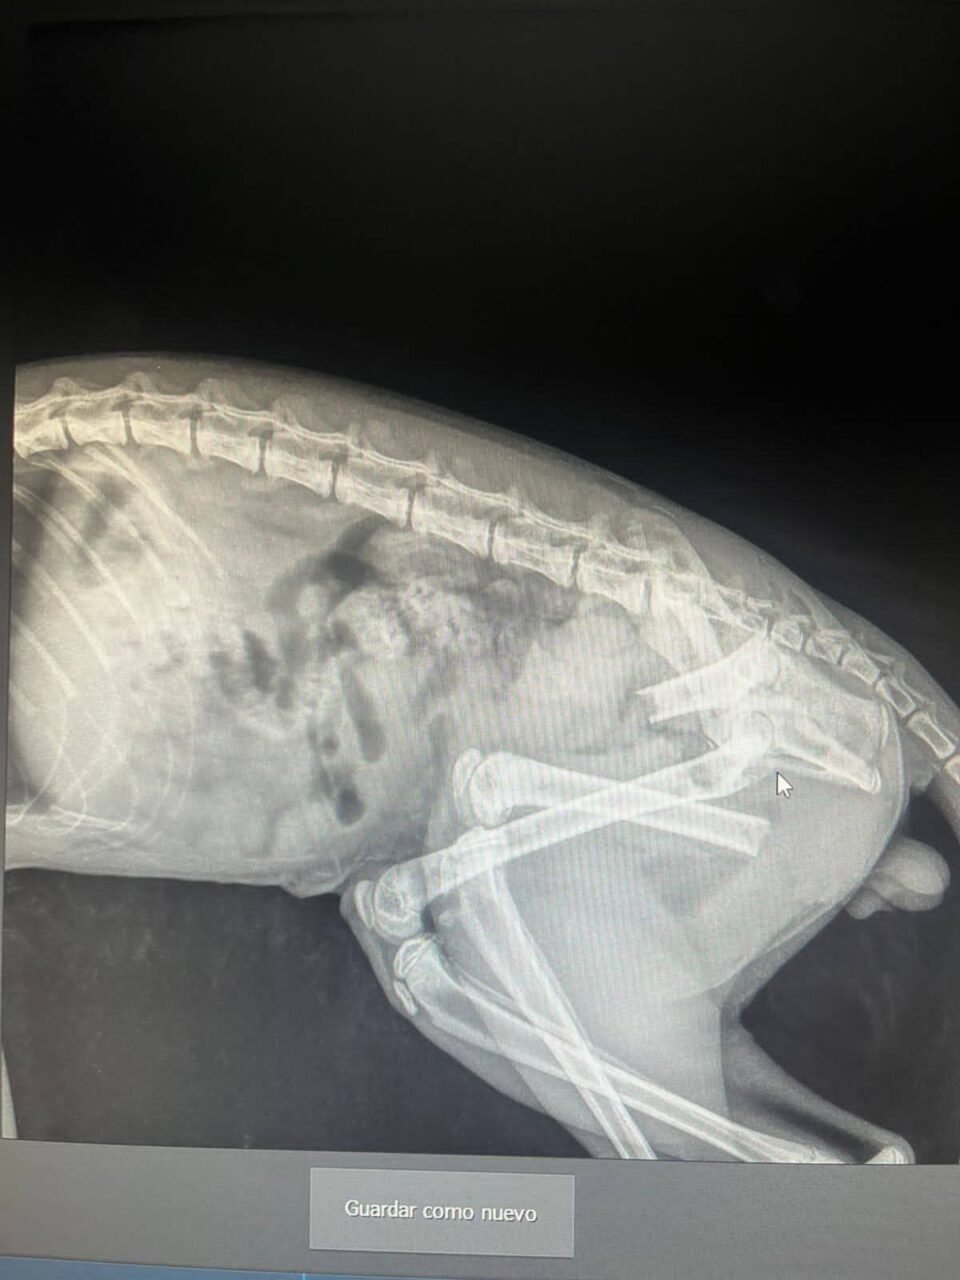

Según el parte veterinario, el pequeño felino corrió con suerte: la punta de la reja no dañó ningún órgano vital, aunque sí afectó su fémur, por lo que será sometido a cirugía próximamente y quedó internado. Posteriormente, se logró ubicar a sus familiares.